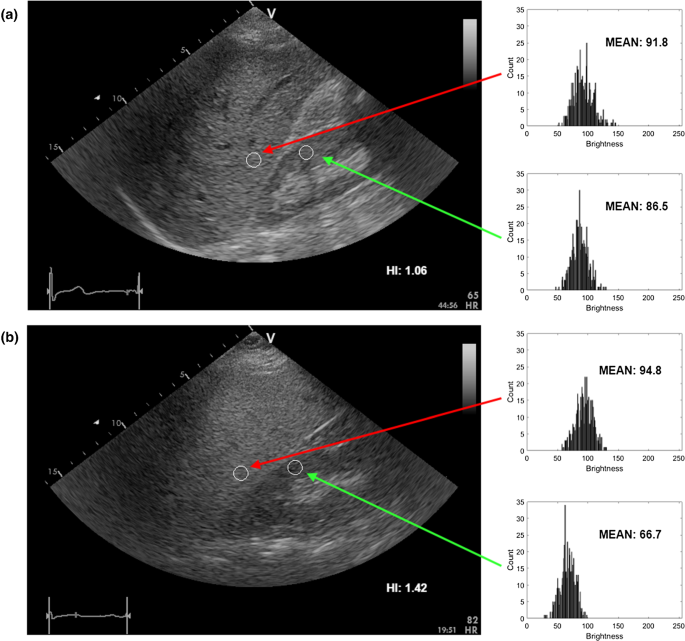

Liver B-mode images and the ROIs selected for HI calculation, a steatosis level of 3% and b 25%, respectively

Hepatorenal index

The HI is defined as the ratio of average brightness level of the liver and the kidney cortex. Generally, the HI is expected to increase with the steatosis level. In our study, the HI was determined by a physician with experience in ultrasonography and echocardiography research acquisition [25]. The physician was blind to biopsy results. In the first step, a single scan frame from the B-mode sequence was selected by the physician. Next, two regions of interest (ROIs) corresponding to the liver and the kidney cortex were specified. The ROI selection is illustrated in Fig. 2. Care was taken to select liver and kidney ROI in the middle part of the image sector, side by side at the same depth. If infeasible due to suboptimal image quality, liver ROI was selected above kidney ROI with the shortest distance possible. The ROI was determined by using circular method with the radius of the circle equal to 5 mm. In each case, the ROI was as uniform as possible. Regions of non-uniform speckle pattern, vessels or ducts were omitted during the ROI selection procedure. The ratio between the average brightness levels in the ROIs was determined with Matlab software (MathWorks INC, USA) using histogram analysis, see Fig. 2.